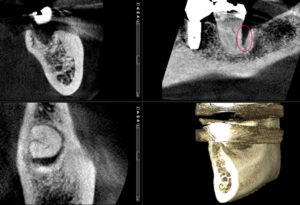

精密歯周治療歯周組織再生療法 Pseudo Papilla Preservation Technique

Before

After

2018.12 before

2022.8 after